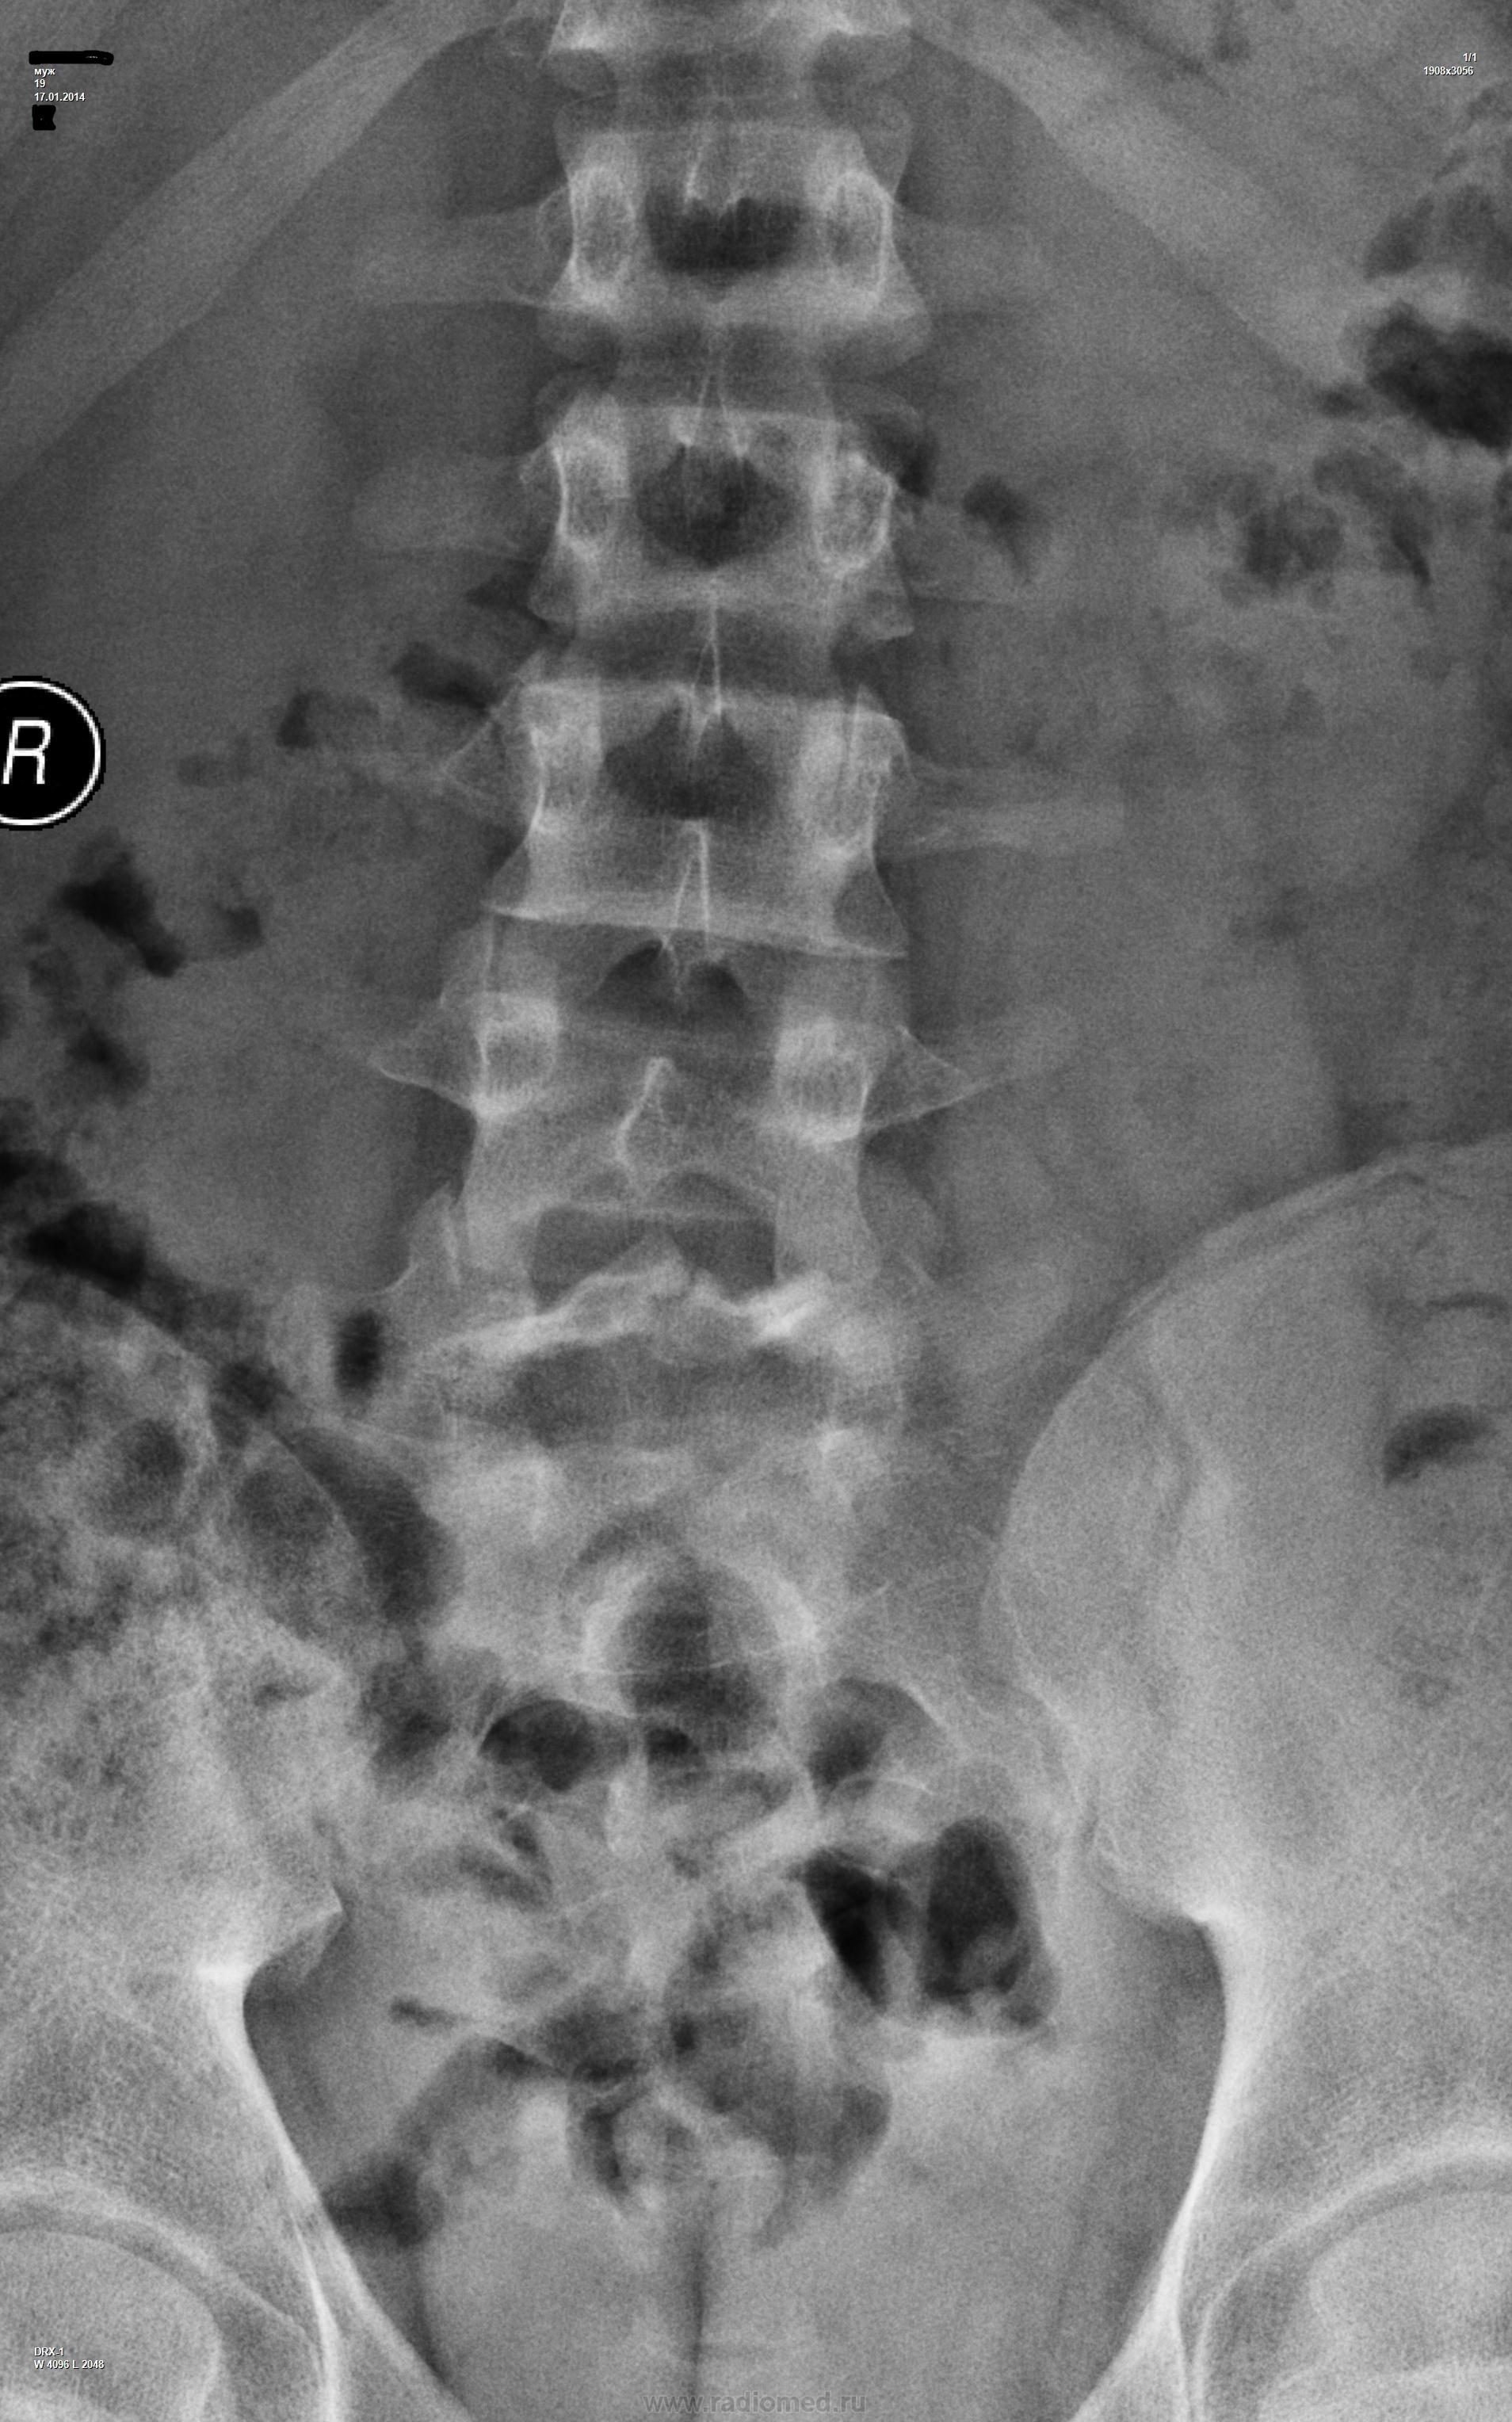

Определяется перед нее смещение L5позвонка с двусторонними дефектами в меж суставных отделах дуги. Незаращение в задних отделах дуг L5 и S1 позвонков. Компрессии тел нет, так же нет смещения других позвонков. Дефекты дуги L5 могут оказаться травматическими или по типу стресс-перелома.

АЛКС не фантазируйте. Передний истинный спондилолистез L5

Вопросов к истинности ни у кого не возникает (чересчур наглядный и поэтому хорошо он читаем), но важен генез - врождённый (незаращение) или травма, то бишь приобретенное будет смещение.

Спондилолистез Л5, спондилолиз. Не перелом же..